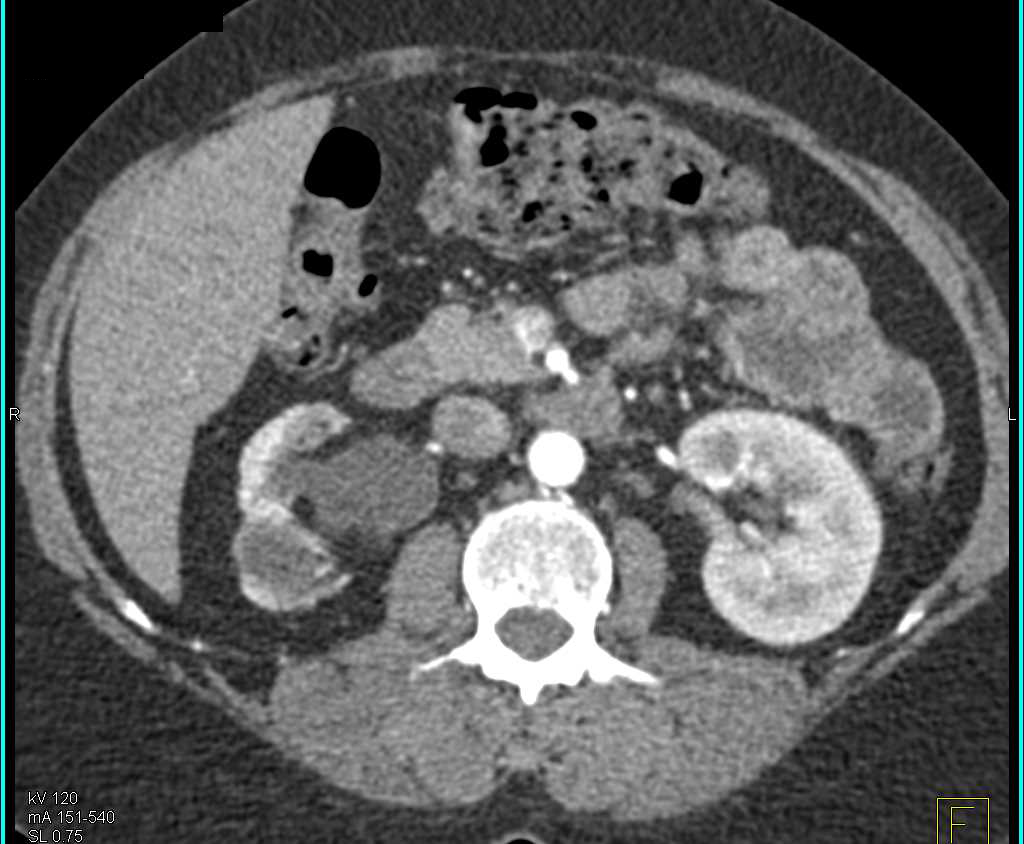

Polycystic Kidney Disease